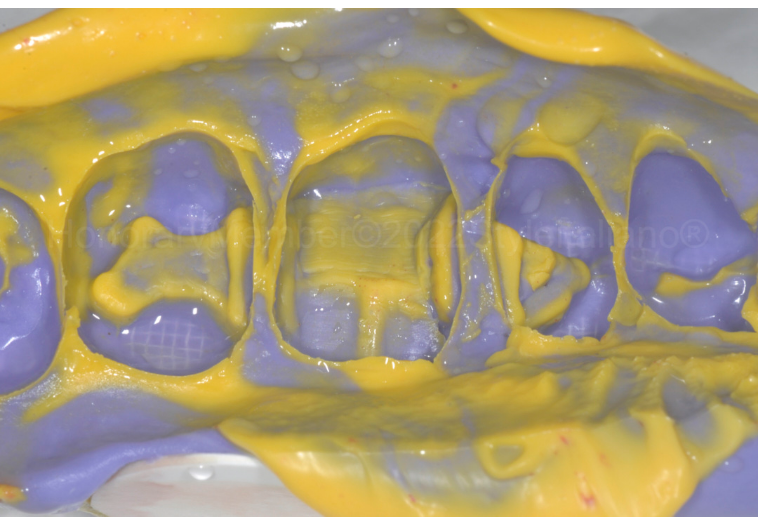

图三:即使GIC对湿性环境不敏感,为了实现深边缘的完美隔离,仍上了橡皮障和金属成型器。这一步骤至关重要,因为它是修复生物相容性的基础。一个塑料楔子被牢固地放置,使金属成型器位于龈壁下方紧贴龈壁,避免血液渗透龈壁。

图四:使用聚丙烯酸在10秒内进行表面处理。然后吹干,并进行表面干燥。

图五:树脂改良型玻璃离子水门汀( DeltaFill , DMG公司)被激活,振动并放置到分配器中,并在邻接区域注射,以覆盖邻面缺损的下部。

图六:为了减少材料的应力,必须进行一分钟的化学固化后,撤除橡皮障,楔子等工具。